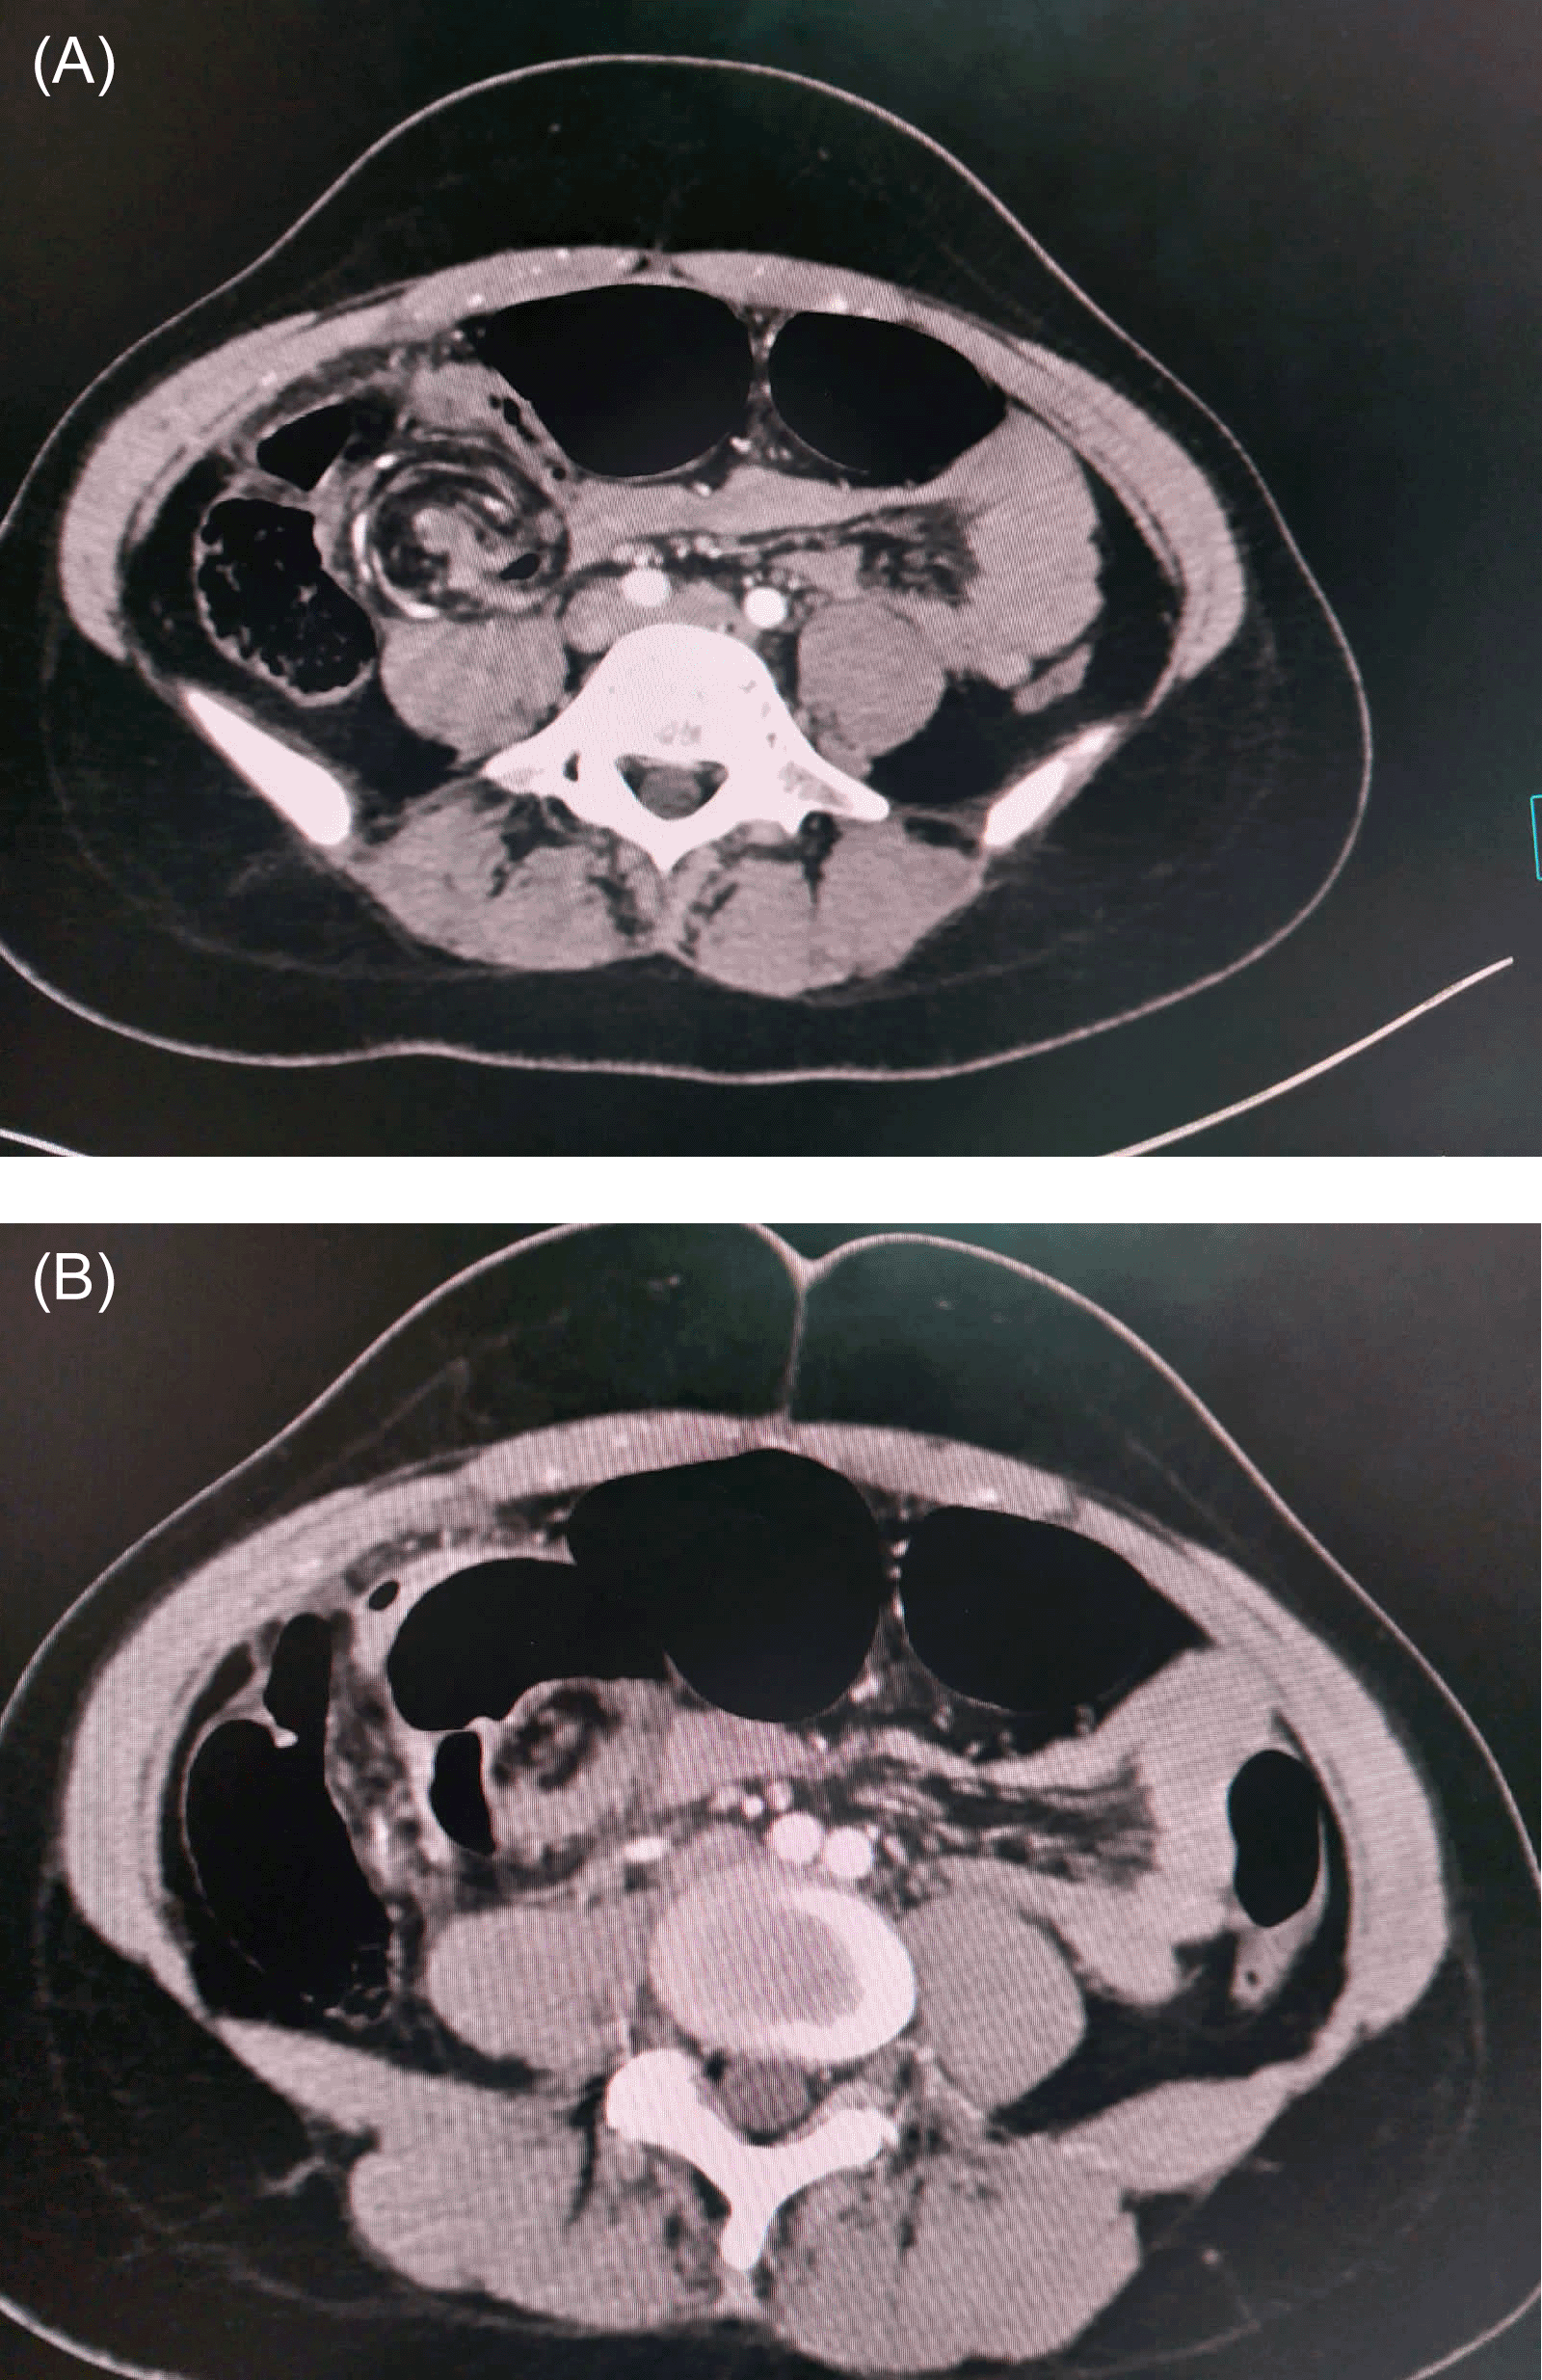

An abdominal computed tomography (CT) scan showed a rounded focal collection of air-distended bowel with haustral creases in the upper left quadrant. In addition, spiralled loops of collapsed cecum (giving a whirl sign) were noted, with low-attenuating fatty mesentery from the twisted bowel (Figure 2).

In terms of diagnosis, CT is the imaging technique of choice, allowing not only confirmation of the diagnosis, but also ruling out other causes of acute obstruction. Coffee bean, bride beak, and whirl signs are the most common observations identified during CT.14